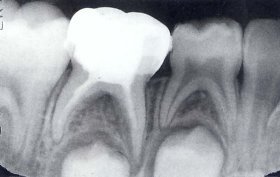

Pulpectomy(乳牙根管治療)

小朋友蛀牙太深故須作根管治療,之後做不鏽鋼乳牙套予以復形.